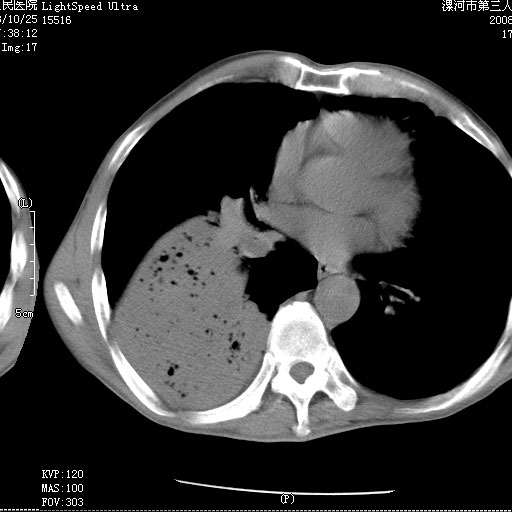

m 老年 发烧、呼吸困难,慢支、肺气肿多年;记的那次是下午大概17:38做的,晚上窒息死亡。

1、右侧脓胸;2、copd;

叶间裂前移,能考虑肺不张和肺栓塞吗?为什么不增强?大叶肺炎不能考虑吗?

右下肺实变,内有弥漫分面小气泡而无支气管征,叶间裂前移,呈臌大之形,而无收缩之状,兼纵隔稍左行移,故。不支持不张,倒支持大叶肺叶,如楼上所说,小气泡不象残留之肺,不可以考虑产气菌感染吗。

坠积性肺炎合并右下肺膨胀不全

右侧脓胸

右下肺阻塞性炎症,内见多发气体影,以肺叶分布.不支持不张.